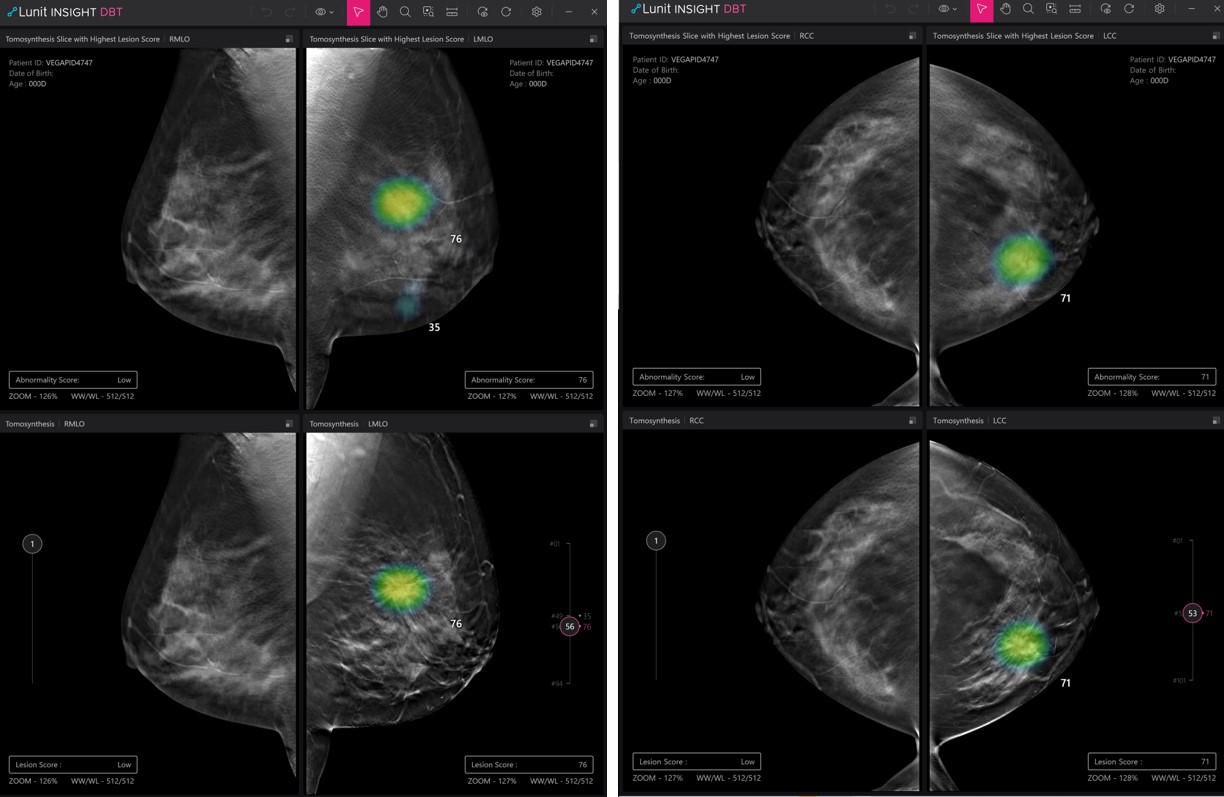

Among the 13 abstracts, three are on Lunit’s newly developed AI solution for digital breast tomosynthesis (DBT), which is the three-dimensional version of the conventional two-dimensional mammography test, rapidly becoming the main screening modality for breast cancer. In the highlight abstract selected to be presented orally, Lunit INSIGHT DBT was demonstrated to have very high accuracy, with an area under the curve (AUC) of 0.943 and sensitivity and specificity of 84.5% and 91.6%, respectively.

Demo image of Lunit INSIGHT DBT